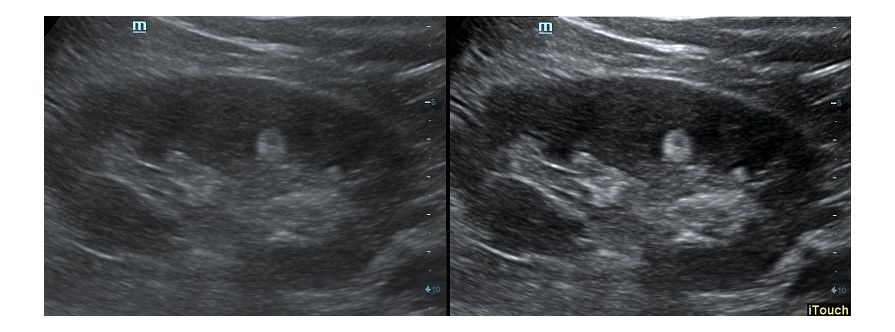

Оптимизация изображения происходит и за счет постобработки. Наиболее часто используемый инструмент - общее усиление (Gain). Усиление делает изображение «ярче», но чем сильнее усиление, тем меньше различия между структурами. Также используются усиление по времени (TGC) и усиление по длине (LGC), которые позволяют изменять отображение на экране послойно, позволяя подсветить гипоэхогенные участки, или, наоборот, снизить визуально эхогенность слишком ярких моментов. Данный вид оптимизации требует много времени, для упрощения работы доктора на приборах Mindray внедрена система автоматической оптимизации - iTouch.